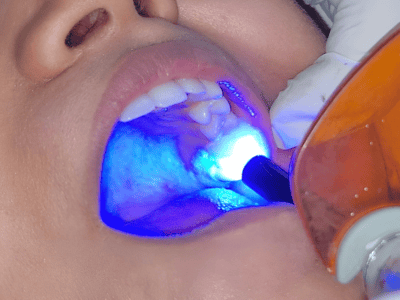

high standards of hygiene and comfort. Her expertise includes laser dentistry, cosmetic smile

We use advanced dental equipment, including laser dentistry, digital X-rays, and minimally invasive techniques, ensuring precision, safety